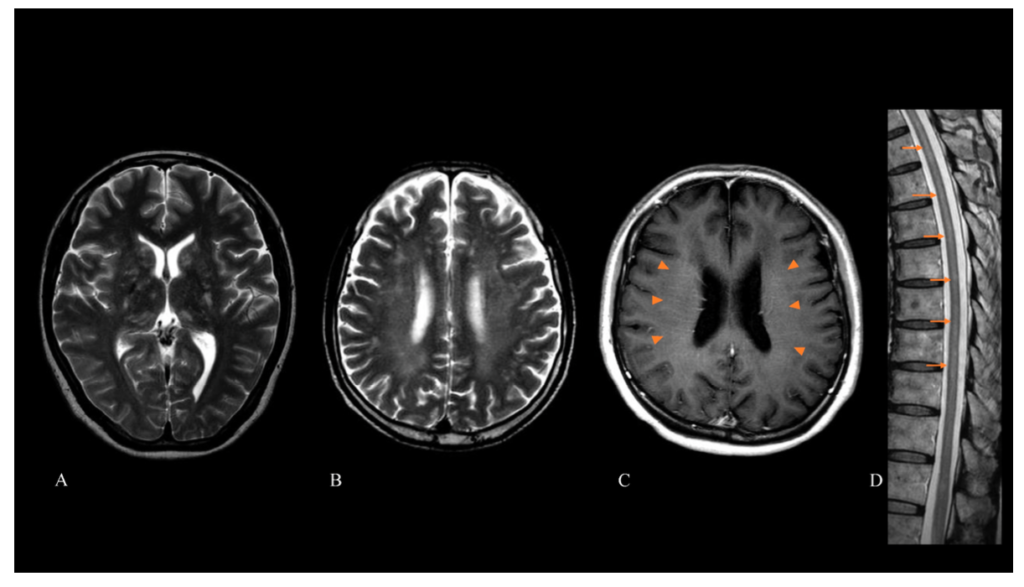

T2/FLAIRの高信号88%(白質58%、基底核43%、小脳6%)

ガドリニウムによる造影所見68%

線状脳室周囲放射状ガドリニウム増強(LPRGE; linear periventricular radial gadolinium enhancement)パターンが約半数に認められる。

*LPRGEはリンパ腫様肉芽腫症・神経サルコイドーシス・中枢神経系血管炎の患者でも報告されている。

脊髄MRI

髄内のT2高信号41%

ガドリニウムによる造影所見47%(髄内24%、髄膜25%)